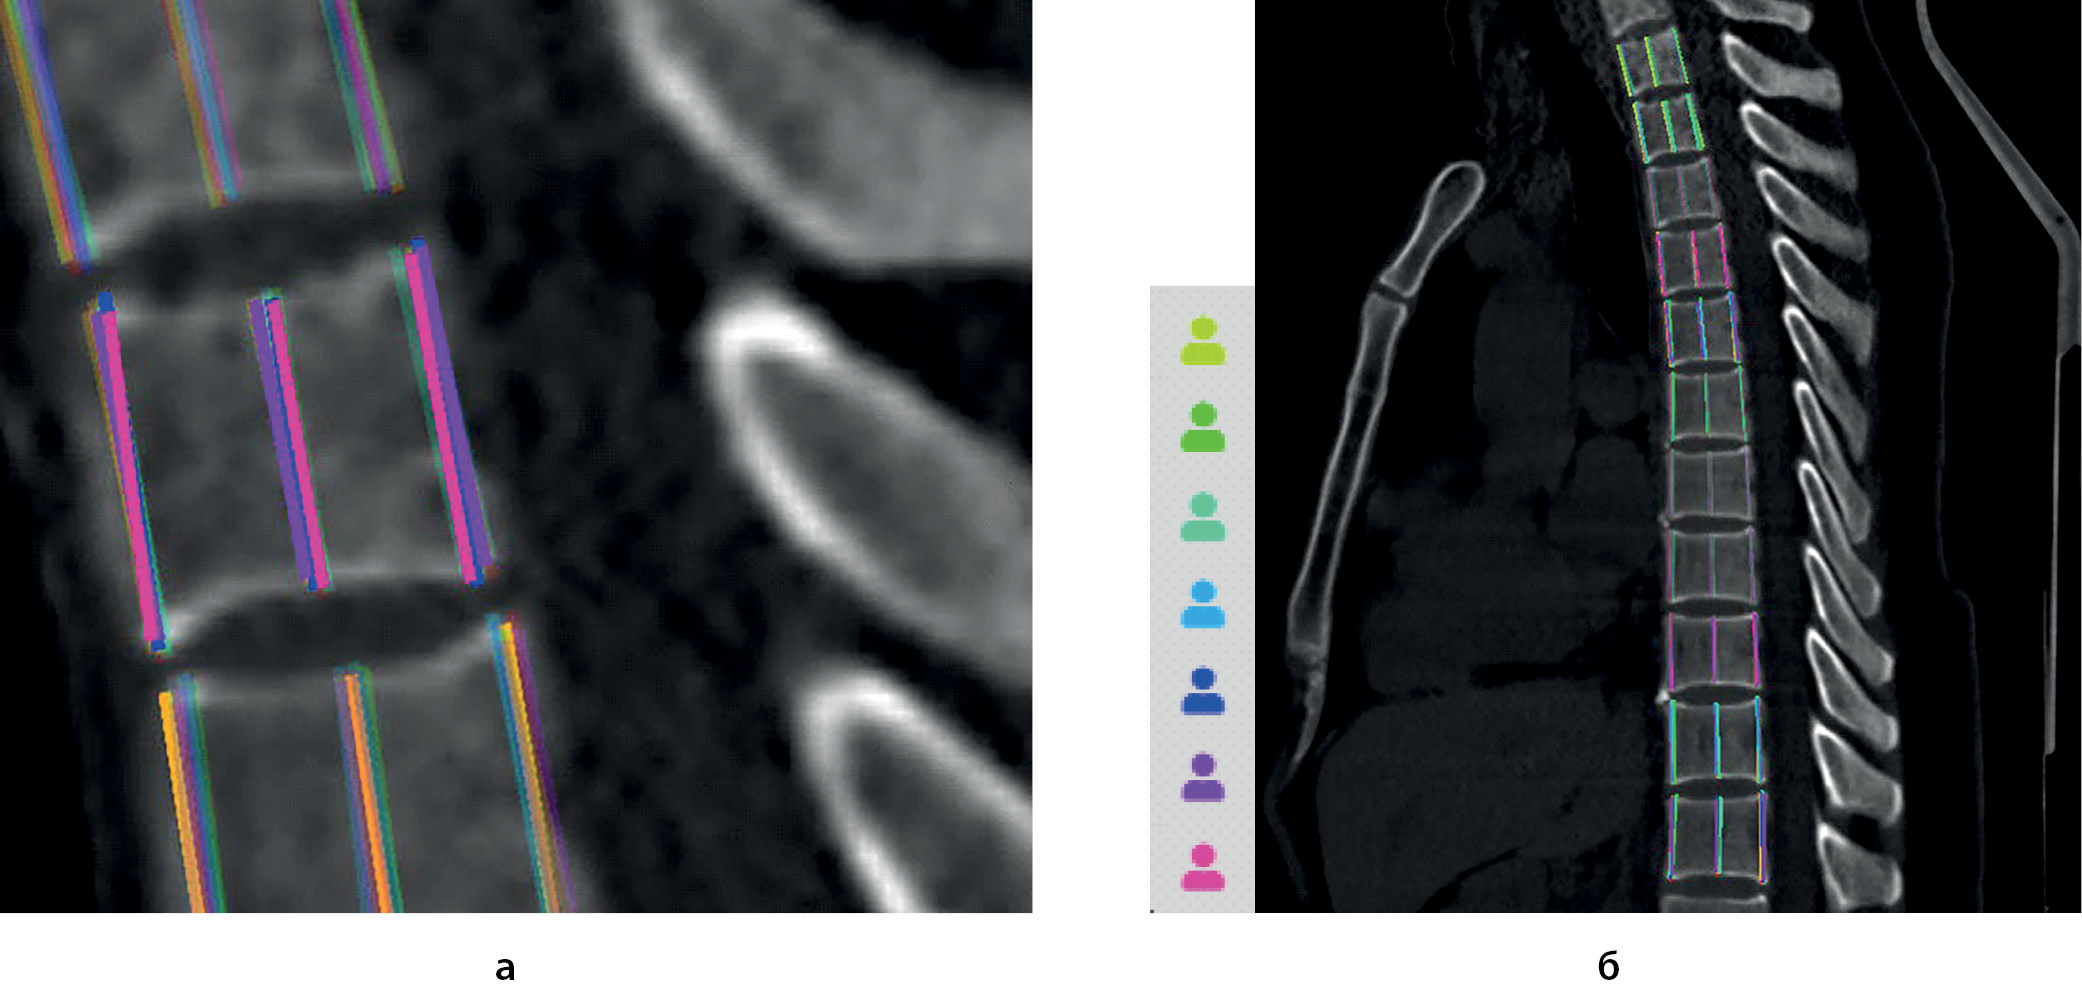

2. Рисунок 2. Пример разметки: а) разметка вентрального, медиального и дорсального размеров отдельного позвонка (ThII); б) Разметка грудного отдела позвоночника от ThI до ThXI. Приведены данные по семи разметчикам, маркированные цветом (интерфейс валидатора, представлены результаты всех разметок). Ярким цветом подсвечены измерения в плоскости реконструкции, более темные измерения в параллельных плоскостях, отражаемые проекционно. | |